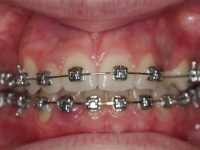

Clase II paciente 15 años

La paciente O.O. acude a nuestra consulta por:

– Canino 13 e incisivo lateral 42 en posición ectópica.

– Canino 23 incluido.

Con lo que decide realizarse un tratamiento de ortodoncia de duración de 24 meses con brackets damon Q.